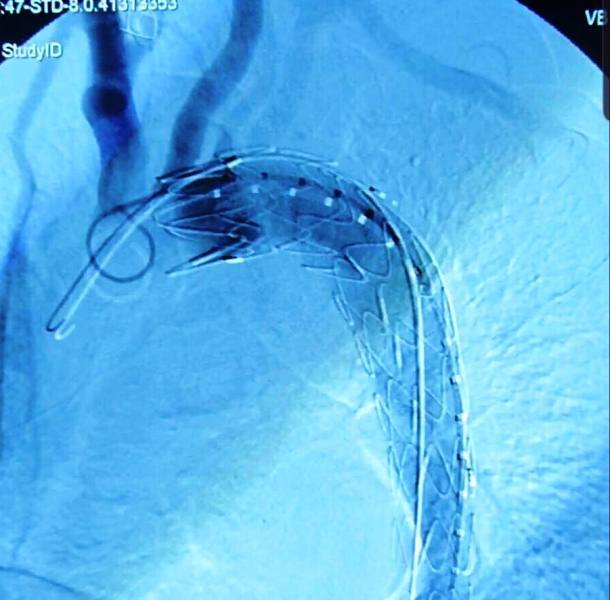

Người đàn ông suýt chết sau tai nạn giao thông khi bị vỡ eo động mạch chủ

Bệnh nhân 42 tuổi sau tai nạn giao thông bị vỡ eo động mạch chủ nguy kịch được các bác sĩ cấp cứu kịp thời giữ lại tính mạng.